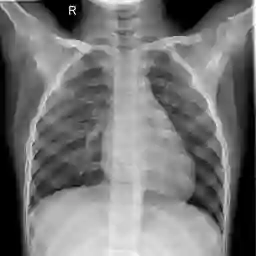

Large numbers of labeled medical images are essential for the accurate detection of anomalies, but manual annotation is labor-intensive and time-consuming. Self-supervised learning (SSL) is a training method to learn data-specific features without manual annotation. Several SSL-based models have been employed in medical image anomaly detection. These SSL methods effectively learn representations in several field-specific images, such as natural and industrial product images. However, owing to the requirement of medical expertise, typical SSL-based models are inefficient in medical image anomaly detection. We present an SSL-based model that enables anatomical structure-based unsupervised anomaly detection (UAD). The model employs the anatomy-aware pasting (AnatPaste) augmentation tool. AnatPaste employs a threshold-based lung segmentation pretext task to create anomalies in normal chest radiographs, which are used for model pretraining. These anomalies are similar to real anomalies and help the model recognize them. We evaluate our model on three opensource chest radiograph datasets. Our model exhibit area under curves (AUC) of 92.1%, 78.7%, and 81.9%, which are the highest among existing UAD models. This is the first SSL model to employ anatomical information as a pretext task. AnatPaste can be applied in various deep learning models and downstream tasks. It can be employed for other modalities by fixing appropriate segmentation. Our code is publicly available at: https://github.com/jun-sato/AnatPaste.